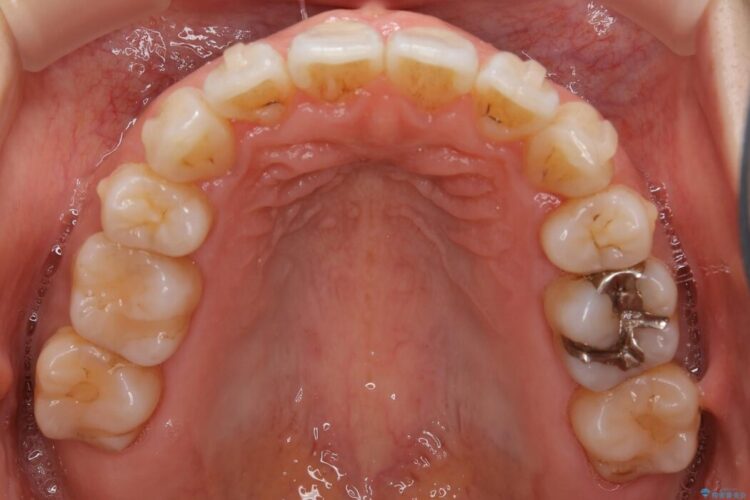

抜歯矯正後の上の前歯の後戻りが気になるとご来院された患者様です。

歯と歯の間を削るのと、歯列のU字型のアーチを僅かに外側に広げる事でスペースを作り、前歯の角度の改善をしました。